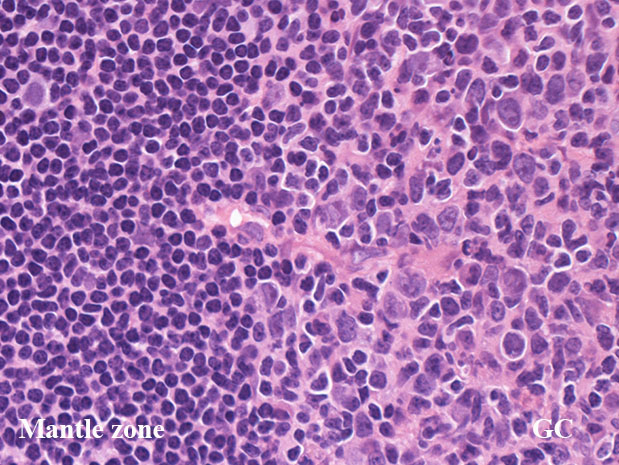

centrocytes(左図), centroblasts(中央, 赤矢印), Mantle zone-GC boder(右図) クリックで拡大図.

centrocyteはくびれや切れ込みのある核をもつ中から大型の細胞で核小体は明瞭なものと不明瞭なものがある.

centroblastは類円形大型のvesicularな核をもったN/C比大の細胞. 核小体が複数個核辺縁にくっつくように認められる.

胚中心には核分裂像やapoptosis像が多く, 正常胚中心のMIB-1 indexは高い。(FLでは low MIB-1 indexとなる. 後述)

腫瘍細胞のほとんどがcentrocyteであっても右図のようにcentroblastを超えるような大型細胞が1個でもあれば,他に大型細胞のみからなる腫瘍性胚中心がないかと,より注意して観察するようにしています。

ほぼすべてがcentroblast/largetransformed cellからできあがっている腫瘍性胚中心があれば,low-grade componentだけではなく,high-grade component(grade 3B)が存在するという診断になります (Dr竹内賢吾談--許可を得て先生の文章をそのままパクり)

低倍率像で濾胞は濾胞間組織にくらべ明るくみえる症例がほとんど。これは小型リンパ球よりやや大型で蒼白な腫瘍細胞が増殖するため。